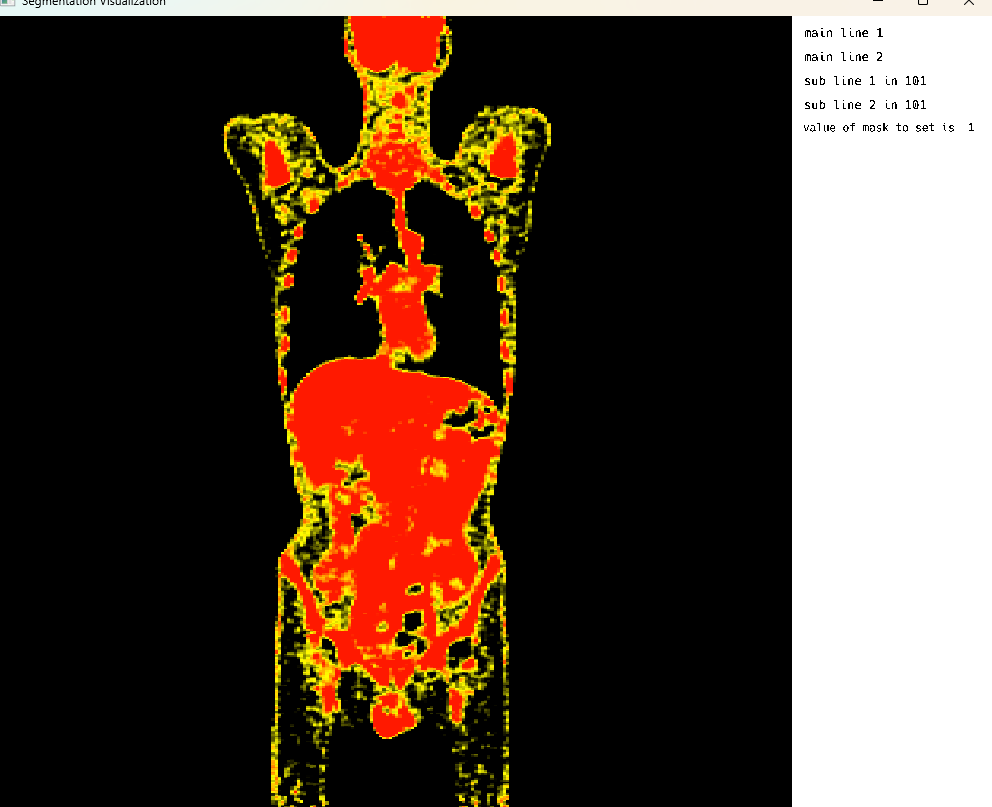

Single Image Display: PET Modality

Single Image Display: PET Modality Visualization

This cell visualizes a PET (Positron Emission Tomography) scan in single image mode. The MedEye3d package displays the medical image data, showing the PET scan in an interactive 3D view. Note that crosshair rendering is currently only supported in multi-image display mode.

using MedEye3d

medEyeStruct = MedEye3d.SegmentationDisplay.displayImage(petImageArg) #singleImageDisplaySingle Image Mode: CT Modality